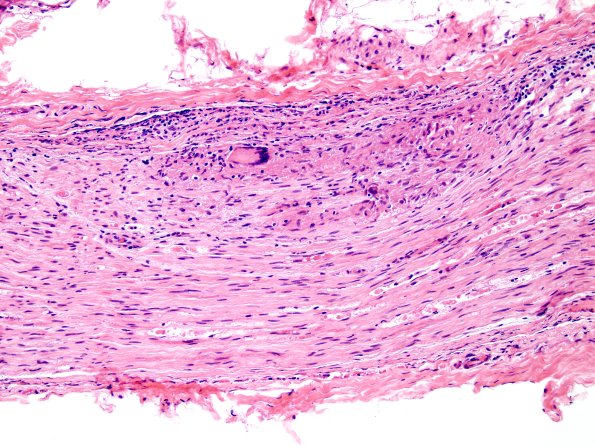

1A6 Sarcoid, no bugs (Case 1) H&E 1

Usually peripheral nerve granulomas in sarcoid do not have multinucleated giant cells but here is an example. (H&E)